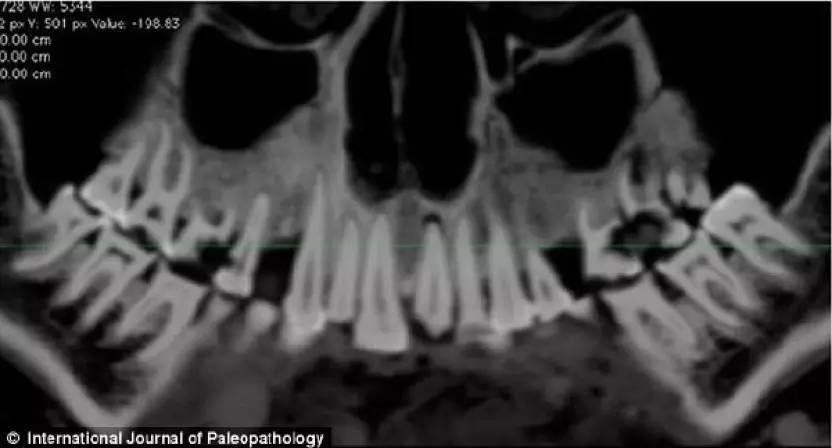

通过对木乃伊头部的CT 扫描成像,

右侧清晰可见用亚麻布塞住的牙洞

2012年,人们对埃及所出土的一具木乃伊头部进行CT扫描,赫然发现了这具距今2100多年的木乃伊独特的地方——上颚骨右侧第一颗和第二颗臼齿之间那个最大的蛀洞里,竟然塞着一片亚麻布!专家认为此举大概是为了隔绝食物。而为了缓解牙痛,用来填充牙洞的亚麻布应该是用无花果汁或者香柏油浸泡过的。